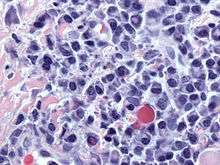

-

_HE_stain.jpg)

Bone marrow aspirate showing the histologic correlate of multiple myeloma under the microscope. H&E stain.

-

Plasmacytoma. H&E stain.

-

Micrograph showing myeloma cast nephropathy in a kidney biopsy. Hyaline casts are PAS positive (dark pink/red - right of image). Myelomatous casts are PAS negative (pale pink - left of image). PAS stain.

-

Atypical plasma cell infiltrate with both Russell (cytoplasmic) and Dutcher (nuclear) bodies (H&E, 50x).

Cellular morphology

The Plasma cells seen in multiple myeloma have several possible morphologies. Typical of plasma cells, they will usually have an eccentric nuclei. Because they are actively producing antibodies, the Golgi apparatus will typically produce a light-colored area adjacent to the nucleus, called a perinuclear halo. The cells may otherwise have the appearance of a normal plasma cell with a single nucleus and a single nucleoli with vesicular nuclear chromatin. Other common morphologies that are seen include:

- Bizarre cells, which are multi nucleated.

- Mott cells, containing multiple clustered cytoplasmic droplets or other inclusions (sometimes confused with auer rods, commonly seen in myeloid blasts)

- Flame cells, having a fiery red cytoplasm.[23] [24]